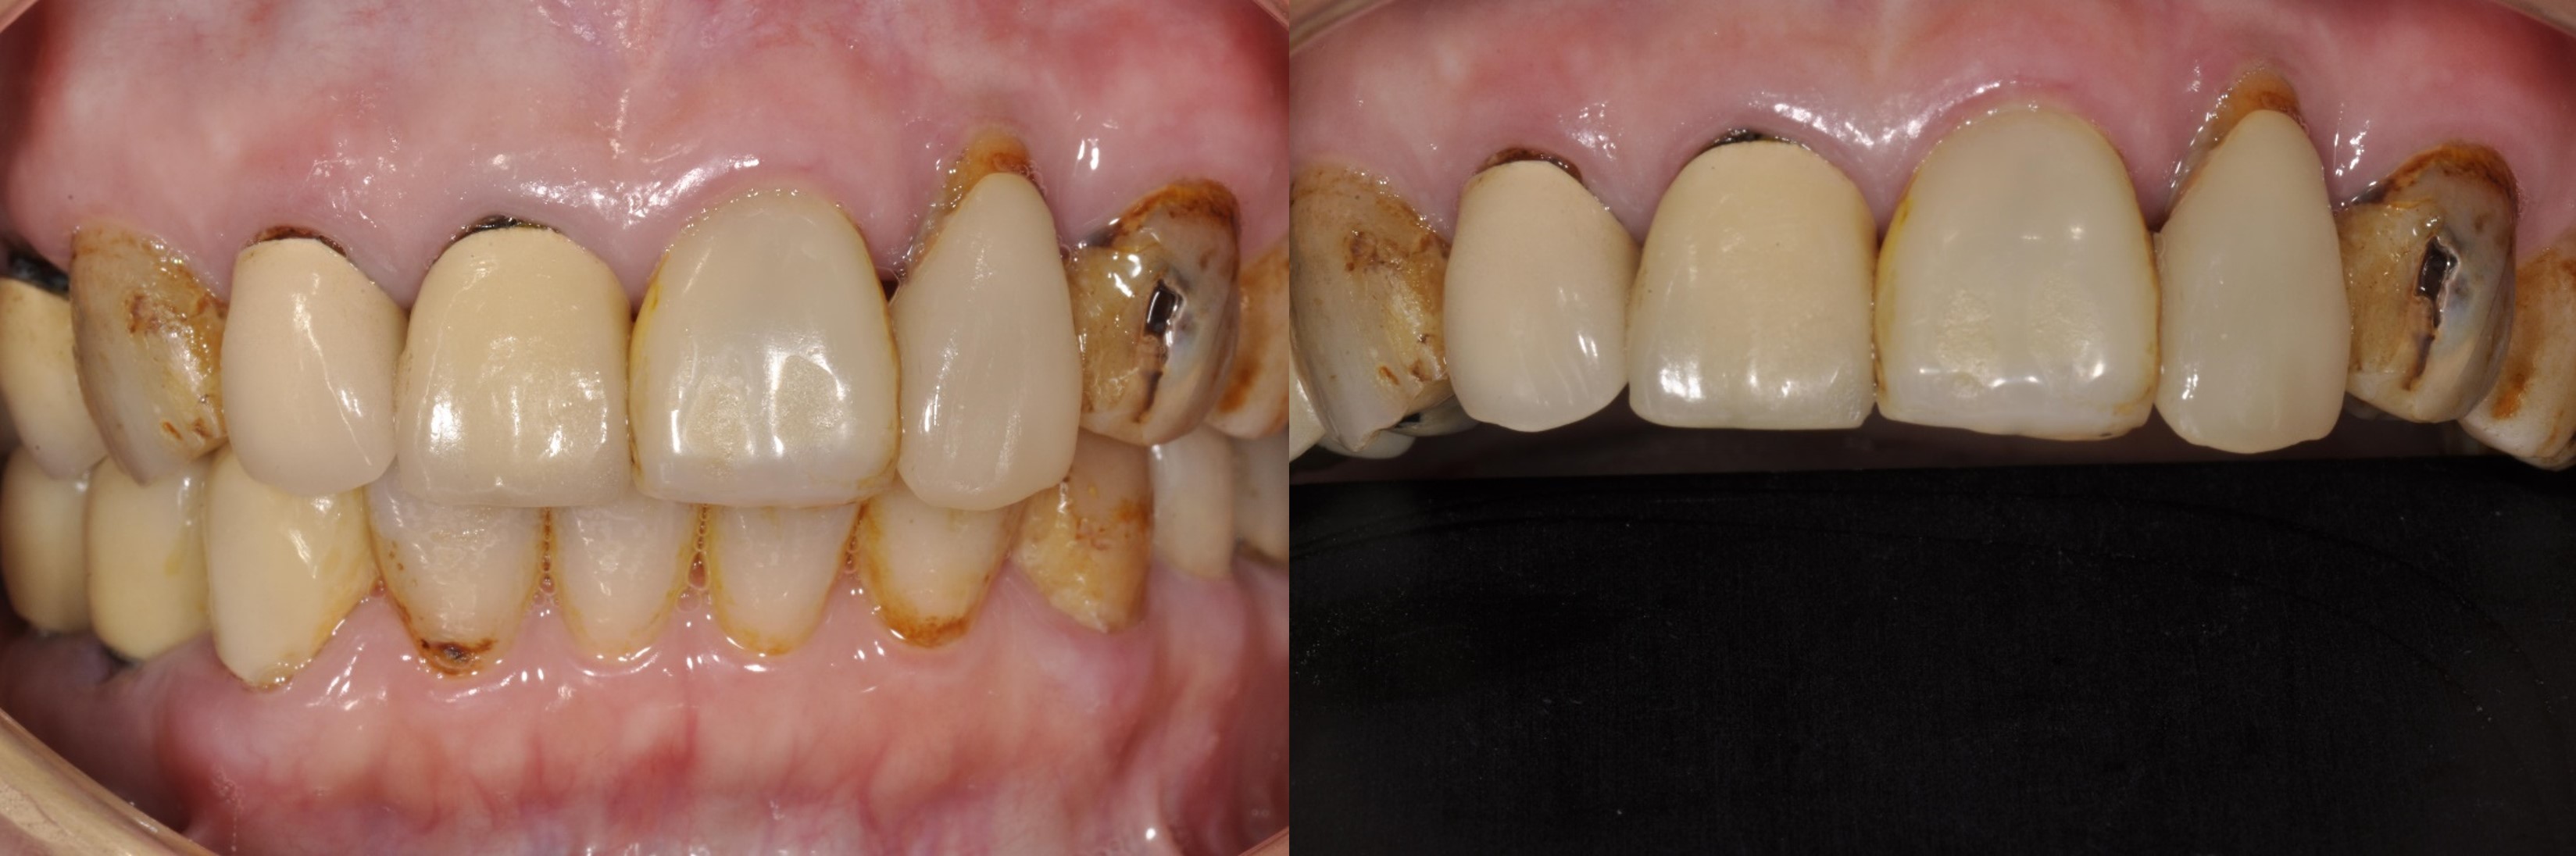

治療前,牙齒再度蛀牙

治療前,牙齒嚴重蛀牙及斷裂

術前、術後比較